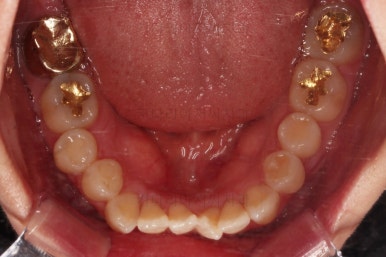

1. 초진

부산개방교합 키다리아저씨치과에 처음 내원 시 입안의 모습입니다.

전반적으로 치열이 삐뚤고요.

어금니 맞물림을 보면 앵글씨 2급 부정교합 양상이어서 위아랫니가 모두 1대1로 부딪히고 있는 상태였습니다.